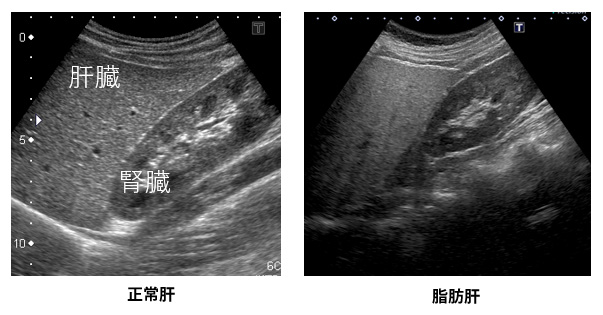

非アルコール性脂肪肝疾患(NAFLD)は、肝臓内の脂肪の蓄積によって引き起こされます。薬物療法と並んで、食事やライフスタイルの変更は最も効果的な管理戦略の 1 つです。

脂肪肝疾患には、アルコール性肝疾患と非アルコール性肝疾患の 2 種類があります。アルコール性脂肪肝は、アルコールの誤用によって引き起こされます。 NAFLDは飲酒とは関係ありません。